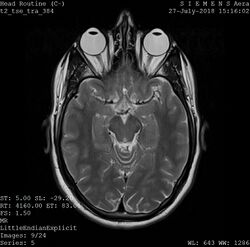

One frame of an MRI scan of the head showing the eyes and brain

A magnetic resonance imaging instrument (MRI scanner), or "nuclear magnetic resonance (NMR) imaging" scanner as it was originally known, uses powerful magnets to polarize and excite hydrogen nuclei (i.e., single protons) of water molecules in human tissue, producing a detectable signal which is spatially encoded, resulting in images of the body.[5] The MRI machine emits a radio frequency (RF) pulse at the resonant frequency of the hydrogen atoms on water molecules. Radio frequency antennas ("RF coils") send the pulse to the area of the body to be examined. The RF pulse is absorbed by protons, causing their direction with respect to the primary magnetic field to change. When the RF pulse is turned off, the protons "relax" back to alignment with the primary magnet and emit radio-waves in the process. This radio-frequency emission from the hydrogen-atoms on water is what is detected and reconstructed into an image. The resonant frequency of a spinning magnetic dipole (of which protons are one example) is called the Larmor frequency and is determined by the strength of the main magnetic field and the chemical environment of the nuclei of interest. MRI uses three electromagnetic fields: a very strong (typically 1.5 to 3 teslas) static magnetic field to polarize the hydrogen nuclei, called the primary field; gradient fields that can be modified to vary in space and time (on the order of 1 kHz) for spatial encoding, often simply called gradients; and a spatially homogeneous radio-frequency (RF) field for manipulation of the hydrogen nuclei to produce measurable signals, collected through an RF antenna.[citation needed]

Like CT, MRI traditionally creates a two-dimensional image of a thin "slice" of the body and is therefore considered a tomographic imaging technique. Modern MRI instruments are capable of producing images in the form of 3D blocks, which may be considered a generalization of the single-slice, tomographic, concept. Unlike CT, MRI does not involve the use of ionizing radiation and is therefore not associated with the same health hazards. For example, because MRI has only been in use since the early 1980s, there are no known long-term effects of exposure to strong static fields (this is the subject of some debate; see 'Safety' in MRI) and therefore there is no limit to the number of scans to which an individual can be subjected, in contrast with X-ray and CT. However, there are well-identified health risks associated with tissue heating from exposure to the RF field and the presence of implanted devices in the body, such as pacemakers. These risks are strictly controlled as part of the design of the instrument and the scanning protocols used.[citation needed]

Because CT and MRI are sensitive to different tissue properties, the appearances of the images obtained with the two techniques differ markedly. In CT, X-rays must be blocked by some form of dense tissue to create an image, so the image quality when looking at soft tissues will be poor. In MRI, while any nucleus with a net nuclear spin can be used, the proton of the hydrogen atom remains the most widely used, especially in the clinical setting, because it is so ubiquitous and returns a large signal. This nucleus, present in water molecules, allows the excellent soft-tissue contrast achievable with MRI.[6][citation needed]

A number of different pulse sequences can be used for specific MRI diagnostic imaging (multiparametric MRI or mpMRI). It is possible to differentiate tissue characteristics by combining two or more of the following imaging sequences, depending on the information being sought: T1-weighted (T1-MRI), T2-weighted (T2-MRI), diffusion weighted imaging (DWI-MRI), dynamic contrast enhancement (DCE-MRI), and spectroscopy (MRI-S). For example, imaging of prostate tumors is better accomplished using T2-MRI and DWI-MRI than T2-weighted imaging alone.[7] The number of applications of mpMRI for detecting disease in various organs continues to expand, including liver studies, breast tumors, pancreatic tumors, and assessing the effects of vascular disruption agents on cancer tumors.[8][9][10]